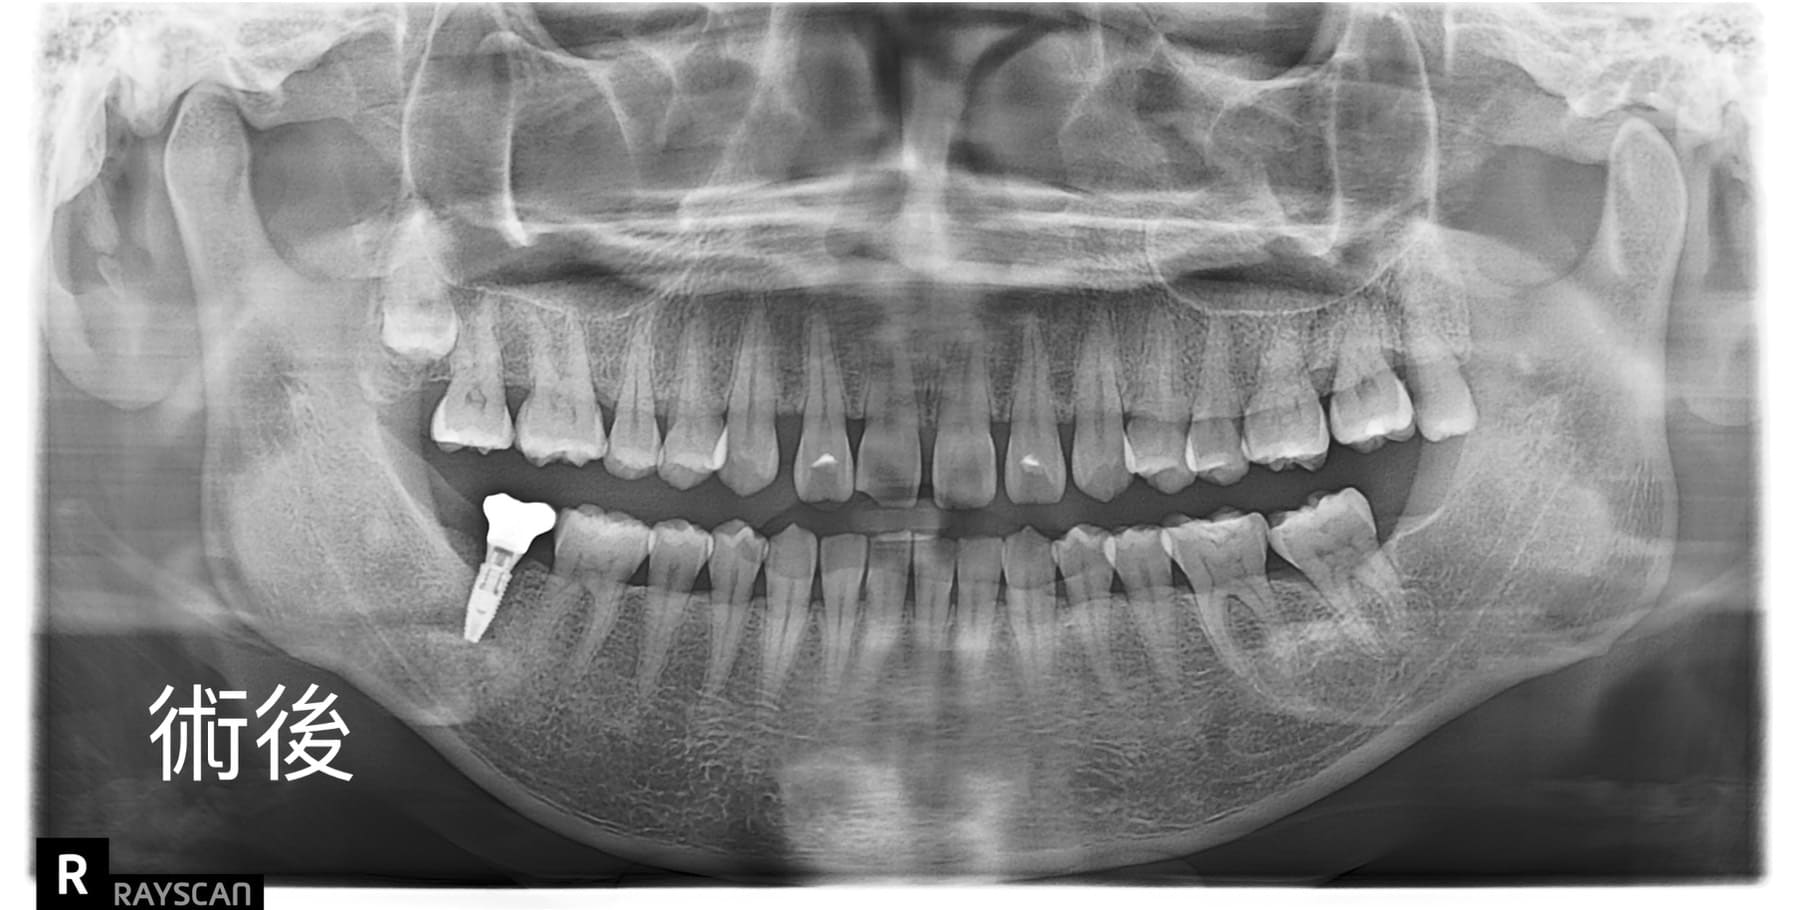

適采牙醫診所數位植牙案例

.jpg)